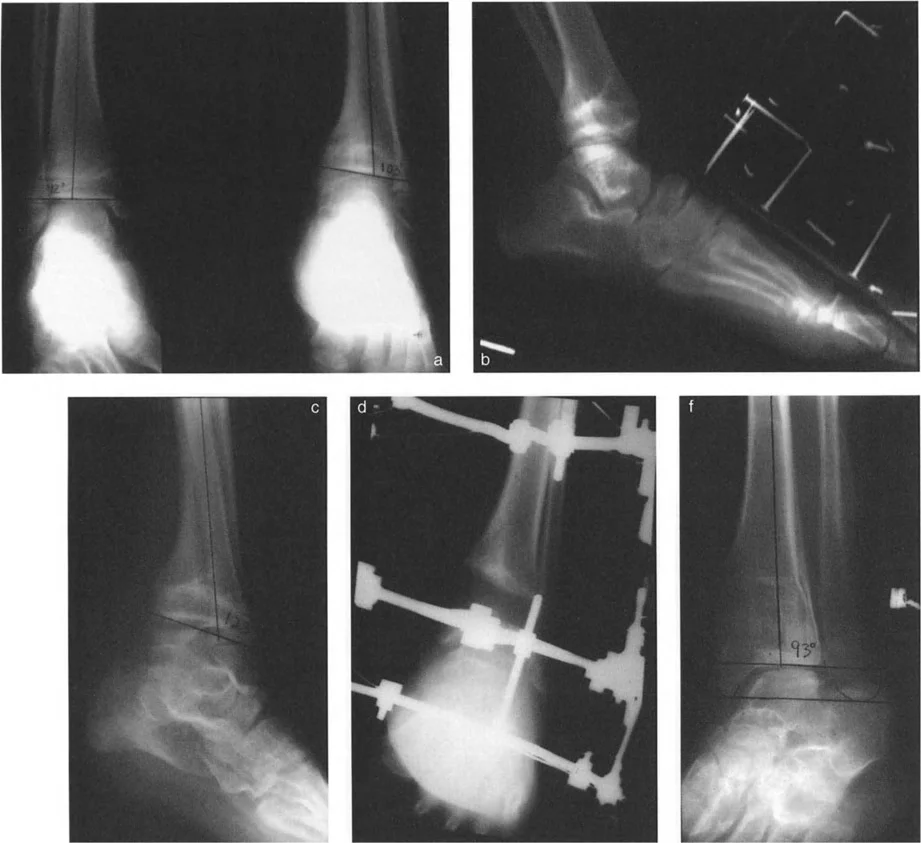

* الأشعة السينية (X-rays) الواقفة لكامل الطرف السفلي: هذه الأشعة ضرورية لتقييم المحاذاة الكلية للطرف السفلي تحت تأثير وزن الجسم. يطلب الأستاذ الدكتور محمد هطيف صورًا شعاعية كاملة الطول للساق أثناء الوقوف (Full-length standing alignment films) لتقييم المحور الميكانيكي للساق وتحديد زوايا المفاصل بدقة.

* الأشعة السينية الجانبية والامامية الخلفية للكاحل: تُظهر هذه الصور تفاصيل مفصل الكاحل نفسه، بما في ذلك زاوية القصبة الأمامية البعيدة (ADTA) وزاوية القصبة الوحشية البعيدة (LDTA)، وهي زوايا حاسمة لتحديد التشوه في المستويين الأمامي والسهمي.

* رسم المحاور الميكانيكية والتشريحية: لتحديد نقطة مركز دوران التشوه (CORA)، وهي النقطة التي يجب أن تتم عندها الجراحة لتصحيح التشوه بأقل قدر من المضاعفات.

جراحة قطع العظم فوق الكاحل (SMO) هي الإجراء الأكثر شيوعًا لتصحيح تشوهات قصبة الساق البعيدة. تتضمن هذه الجراحة قطعًا دقيقًا في عظم الساق (القصبة) فوق مفصل الكاحل مباشرة، ثم إعادة محاذاة العظم وتثبيته في الوضع الصحيح. هناك عدة أنواع من هذه الجراحة: